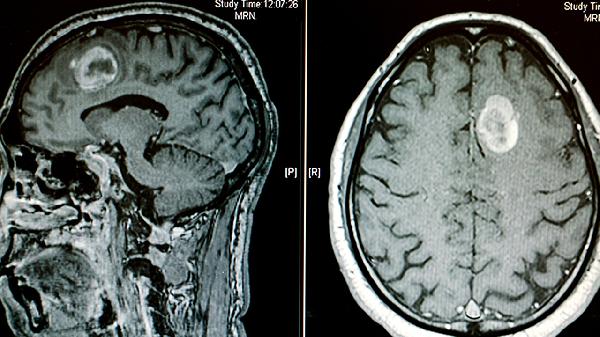

CT检查对脑癌的检出率与肿瘤类型、大小、位置等因素有关。体积较大的脑癌或伴有明显占位效应的肿瘤,CT平扫可能显示低密度或高密度病灶,增强CT能进一步观察肿瘤血供情况。部分低级别胶质瘤、微小转移灶或位于颅底等特殊区域的肿瘤,CT可能难以清晰显示。脑癌可能表现为头痛、呕吐、视力模糊、肢体无力等症状,若CT未发现异常但症状持续,需进一步检查。

磁共振成像对软组织分辨率更高,能更敏感地发现早期脑癌,尤其是多模态MRI可鉴别肿瘤性质。PET-CT可评估肿瘤代谢活性,辅助判断良恶性。脑脊液检查对某些脑膜癌病有诊断价值。立体定向活检是确诊脑癌的金标准,通过病理分析明确肿瘤类型与分级。对于疑似脑癌患者,医生会根据临床表现综合选择检查手段。